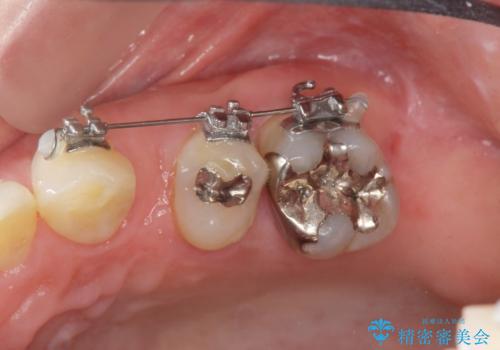

補綴前小矯正について

矯正を行うことで歯を適切な位置に動かすことでより、清掃性に優れ長期的な予後を見込むことのできるブリッジを製作することができました。